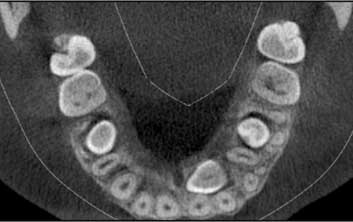

- • La distance a été mesurée dans le plan transversal sur les coupes axiales au niveau du CBCT à 1 mm près.

- • Ensuite, cette largeur maximale du follicule dentaire de la canine a été classée par intervalles de 1 mm en 4 grades (10):

- - Grade 1: de 0 à 1 mm (Fig 7),

- - Grade 2: de 1 à 2 mm (Fig 8),

- - Grade 3: de 2 à 3 mm (Fig 9),

- - Grade 4: > à 3 mm (Fig 10).